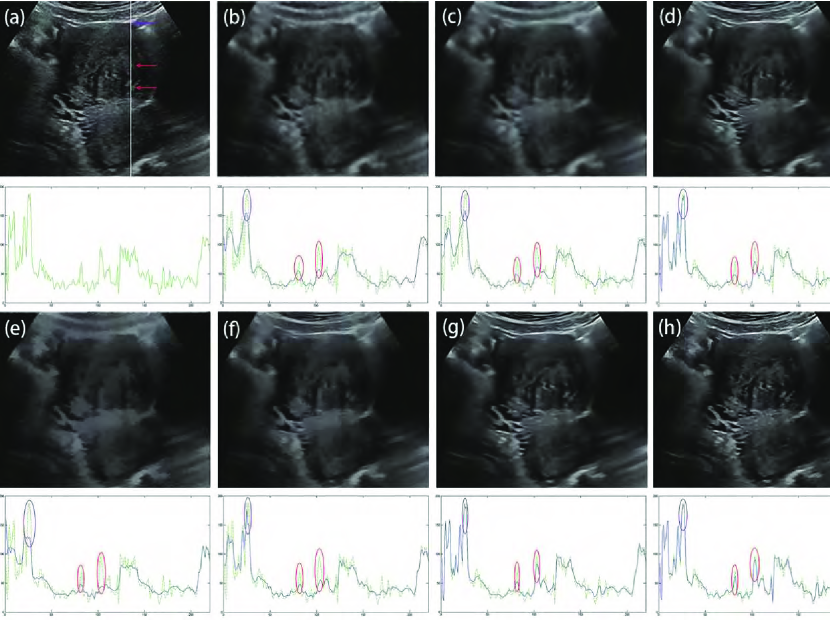

To more closely evaluate despeckled images of different filters, we adopted the method in [69] which evaluates all the features located in a single scan line through the ultrasound image. Fig. 8 shows the despeckled images of different filters and their corresponding intensity value profile at the same scan line (marked as white solid line across the image in Fig. 8(a)). The intensity profile of scan line shows that, Frost, SRAD, SBF and ADLG all fail to maintain the edge contrast, reducing the visual effect. OBNLM and NLLRF succeed in enhancing the high-contrast edges in regions of interest (ROI) shown by the purple window. For low-contrast edges indicated by the red windows, both the OBNLM and NLLRF methods fail to preserve the local contrast of edge. As shown by the ROI in red windows in Fig. 8(h), after edge enhancement using adaptive fractional-order , there are slight differences of edge contrast between the despeckled image of the PFDTV method and the original ultrasound image. Compared with other filters, the PFDTV method achieves the best performance in preserving the edge contrast. More despeckled results are depicted in Fig. 9. Obviously, the PFDTV method removes speckle noise thoroughly while preserving features satisfactorily.